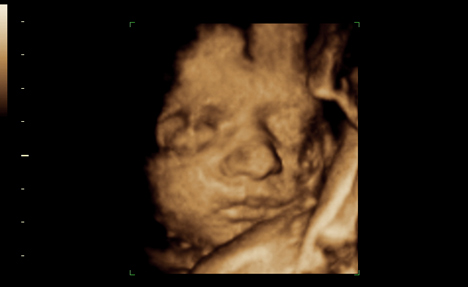

Les progrès dans l’utilisation des ultrasons ont aussi dopé le phénomène. «Avec l’échographie tridimensionnelle, on n’obtient plus un profil mais quasiment une photo du visage de l’enfant», relève Yvan Vial, médecin chef du service d’obstétrique et responsable de l’unité d’échographie du CHUV. L’échographie reste un outil diagnostique, mais si l’enfant est bien positionné, le résultat devient photogénique et particulièrement émouvant. «Notre société valorise tellement l’image, n’est-il pas logique que les futurs parents veuillent partager celles qu’ils ont de leur bébé?», interroge le spécialiste.